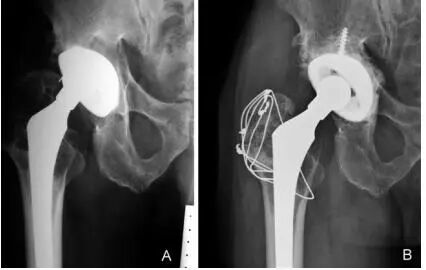

图6:A和B,一位69岁男性假体周围骨盆骨溶解,无骨水泥全髋关节置换术后12年的大转子和小粗隆的右髋位X线片。A:翻修手术前的x光片。B组:髋臼假体翻修一年后行大转子切开复位内固定,2根张力带钢丝和1根斜环扎钢丝,辅以异体骨移植,显示大转子骨折愈合。